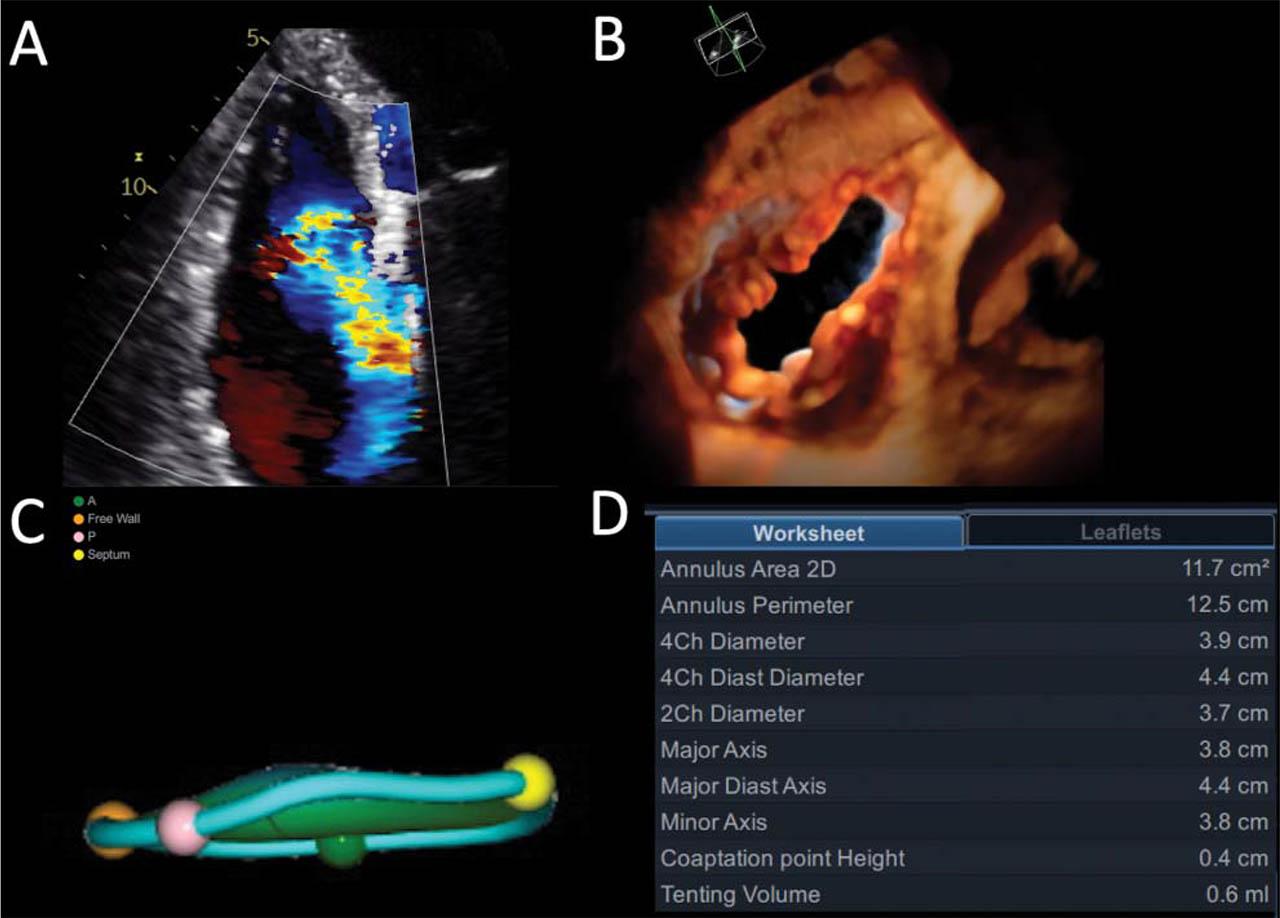

Figure 2

Atrial functional tricuspid regurgitation: RV-focused apical four-chamber color flow of the regurgitant jet (A); En face view of the tricuspid valve by 3D echocardiography (B); Tricuspid annulus geometry (C) and measurements (D) by 4D Auto TVQ software (GE Healthcare, Horten, N).